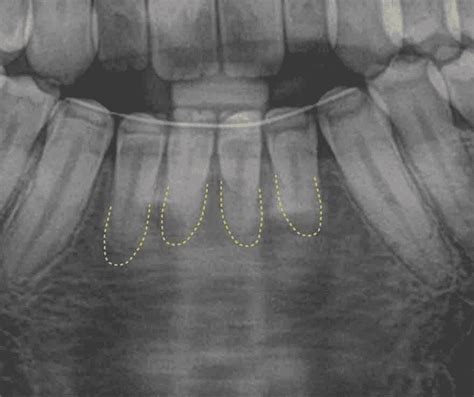

La reabsorción radicular es un proceso patológico en el cual las células del cuerpo comienzan a degradar y reabsorber el tejido de las raíces de los dientes. Este fenómeno puede ocurrir tanto en dientes permanentes como en dientes temporales (de leche), afectando la dentina y la pulpa dentro de la raíz (reabsorción interna) o el cemento y la superficie externa de la raíz (reabsorción externa).

Existen varias causas posibles para la reabsorción radicular, que incluyen traumatismos dentales, enfermedades periodontales, presión excesiva en los dientes debido a la mordida irregular o maloclusión, inflamación crónica en la pulpa dental, y factores genéticos. Este proceso puede llevar a la pérdida de la raíz dental y, en casos graves, a la movilidad o pérdida del diente afectado.

La pérdida de dientes de leche y la aparición de los dientes definitivos es un proceso natural en el desarrollo de los niños. Para que se produzca este proceso conocido como recambio dentario, el diente definitivo debe ir reabsorbiendo (comiéndose) la raíz del diente de leche en su camino desde la zona donde se ha formado dentro del hueso hasta que lo vemos en boca.

Una de las razones más frecuentes por las que un diente definitivo no sale es una alteración en la reabsorción de la raíz del diente de leche. Cuando esto ocurre el diente de leche no se cae a tiempo y el permanente al no tener sitio para salir sale en un lugar alejado del ideal o se queda retenido dentro del hueso.